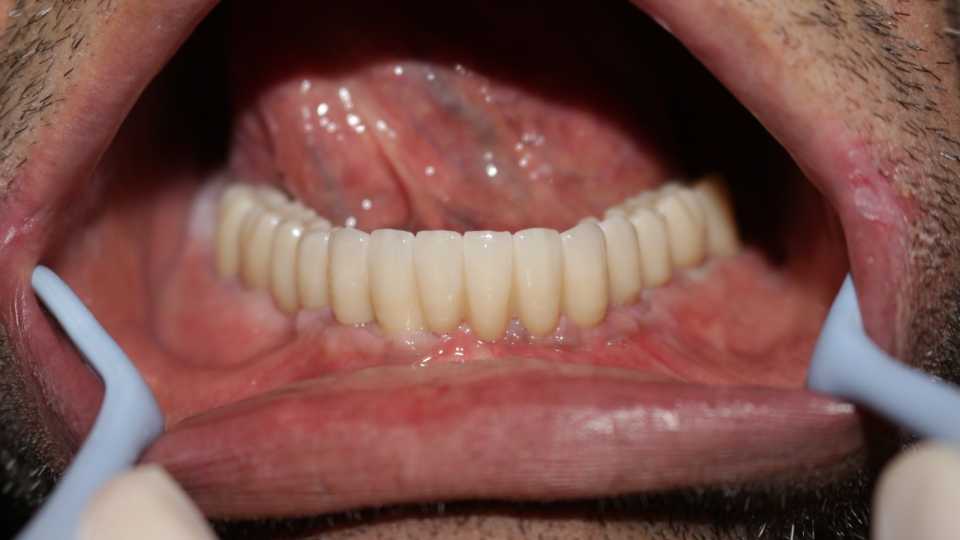

Pacientul Nicu D., în vârstă de 50 de ani, s-a prezentat în cabinet cu o edentație totală mandibulară în urma unei boli parodontale.

Împreună cu pacientul am hotărât realizarea unei lucrări protetice fixe inșurubabile pe 6 implanturi (implanturi Paltop). Lucrarea a fost realizată din ceramică pe zirconiu.

Implantul Paltop oferă posibilitatea realizării unor lucrări cu o estetică impecabilă și o afectare minimă a țesuturilor la locul implantării. Profilul concav al bontului protetic ajută la formarea unui țesut gingival dens la nivelul legăturii transgingivale scăzând vizibilitatea bontului.